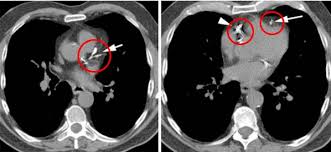

3. 진단 방법 – CAC 스코어

- 비침습적 **관상동맥 칼슘 스캔(칼슘 스코어 CT)**로 Agatston score 산출 :contentReference[oaicite:6]{index=6}.

- 0 = 이상 없음, 1–99 = 경증, 100–399 = 중등도, ≥400 = 중증으로 분류되며, 점수가 높을수록 심혈관 위험이 증가합니다 :contentReference[oaicite:7]{index=7}.

- 중등도 이상일 경우 관상동맥 협착 위험이 높으며, 추가 정밀검사 및 적극 치료가 필요합니다 :contentReference[oaicite:8]{index=8}.

- CT 스캔은 빠르고(약 15분), 고해상도이며, 진단·예후 판단에 유용합니다 :contentReference[oaicite:9]{index=9}.

- 정밀 수술적 치료: 중증 석회화 시 PCI(풍선·스텐트), IVL (intravascular lithotripsy), 관상동맥우회술 고려 :contentReference[oaicite:15]{index=15}.